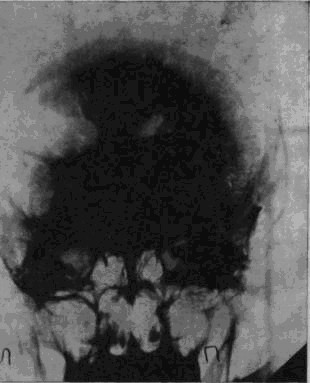

«Младший лейтенант Засецкий, 23 лет, получил 2 марта 1943 года пулевое проникающее ранение черепа левой теменно-затылочной области. Ранение сопровождалось длительной потерей сознания и, несмотря на своевременную обработку раны в условиях полевого госпиталя, осложнилось воспалительным процессом, вызвавшим слипчивый процесс в оболочках мозга и выраженные изменения в окружающих тканях мозгового вещества».

Осколок внедрился в вещество задних, теменно-затылочных отделов мозга и разрушил мозговую ткань этой области.

Ранение осложнилось воспалительным процессом; он не распространенный, местный, ограничен лишь областями мозга, примыкающими к непосредственному месту ранения, но теменно-затылочные отделы левого полушария, отделы, так тесно связанные с анализом пространственного мира, необратимо повреждены, и уже начинается процесс образования рубцов, который неизбежно повлечет за собою частичную атрофию расположенных вблизи ранения участков мозгового вещества.

Рис. 16. Черное пятно в правом полушарии – осколок, расположенный под кожей от поверхностного шрапнельного ранения, полученного им за год до основного ранения

И через десять лет после ранения – еще одна выписка из истории болезни, на этот раз сделанная на основе рентгенограммы.

В спинномозговой канал введен воздух. Он поднялся вверх, заполнил контуры желудочков мозга и те пустоты, которые образовались в результате сморщивания вещества отделов мозга, непосредственно примыкающих к месту ранения. «Процесс рубцевания вызвал атрофические изменения в левом боковом желудочке. Стенки его подтянуты к поверхности мозга, подоболочечные пространства резко расширены. Значительный местный атрофический процесс».

Ранение вызвало местную атрофию мозгового вещества левой теменно-затылочной области.